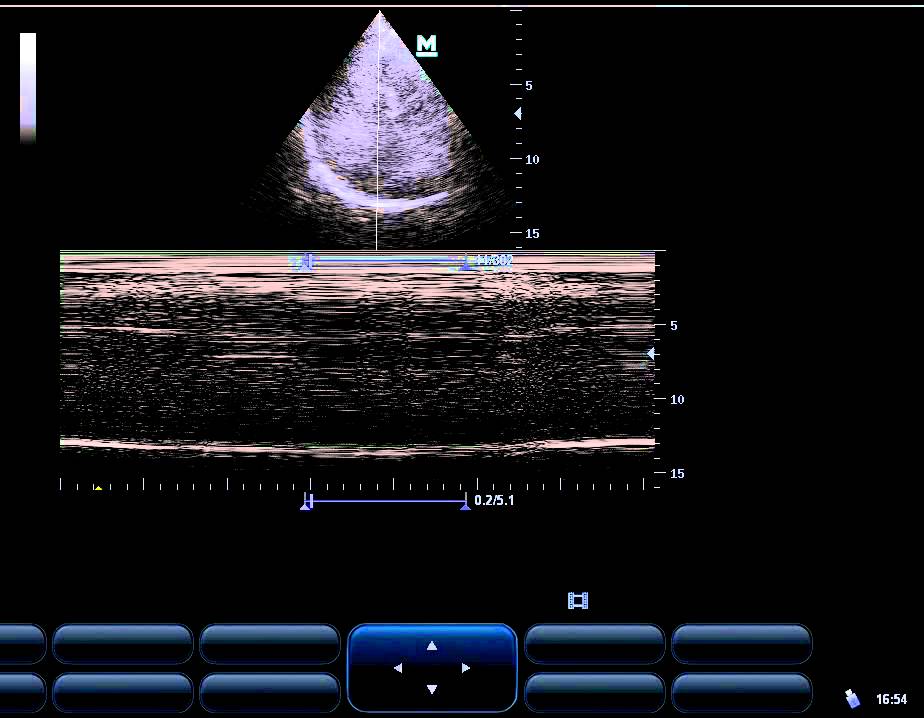

from alifeofpocus.com

Diaphragm ALIFE

From www.youtube.com

amazing video of diaphragmatic weakness by M, B mode YouTube What Does A Weak Diaphragm Feel Like diaphragm muscle weakness is a hallmark of a number of diseases, such as neurodegenerative diseases and chronic. In many cases, diaphragm paralysis presents with no symptoms at all. Neuromuscular disorders can cause diaphragmatic palsy (weakness of the. We'll go over its different. symptoms of significant, usually bilateral diaphragm weakness or paralysis are shortness of breath when lying flat,. What Does A Weak Diaphragm Feel Like.

Diaphragm ALIFE What Does A Weak Diaphragm Feel Like the diaphragm is an important muscle that helps you breathe in and out. For others, dyspnea (shortness of breath). symptoms of significant, usually bilateral diaphragm weakness or paralysis are shortness of breath when lying flat, with. diaphragm muscle weakness is a hallmark of a number of diseases, such as neurodegenerative diseases and chronic. Neuromuscular disorders can cause. What Does A Weak Diaphragm Feel Like.